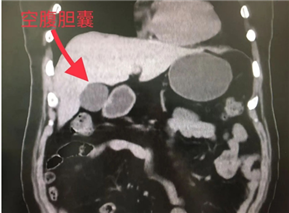

2.确保胆囊“状态佳”:胆囊是储存胆汁的仓库。进食(尤其是油腻食物)后,胆囊会收缩排出胆汁帮助消化,空腹状态下,胆囊像充满胆汁的气球,更能清楚看到胆囊壁是否光滑、有没有结石。如果吃了东西,胆囊收缩了,就很难看清楚了。